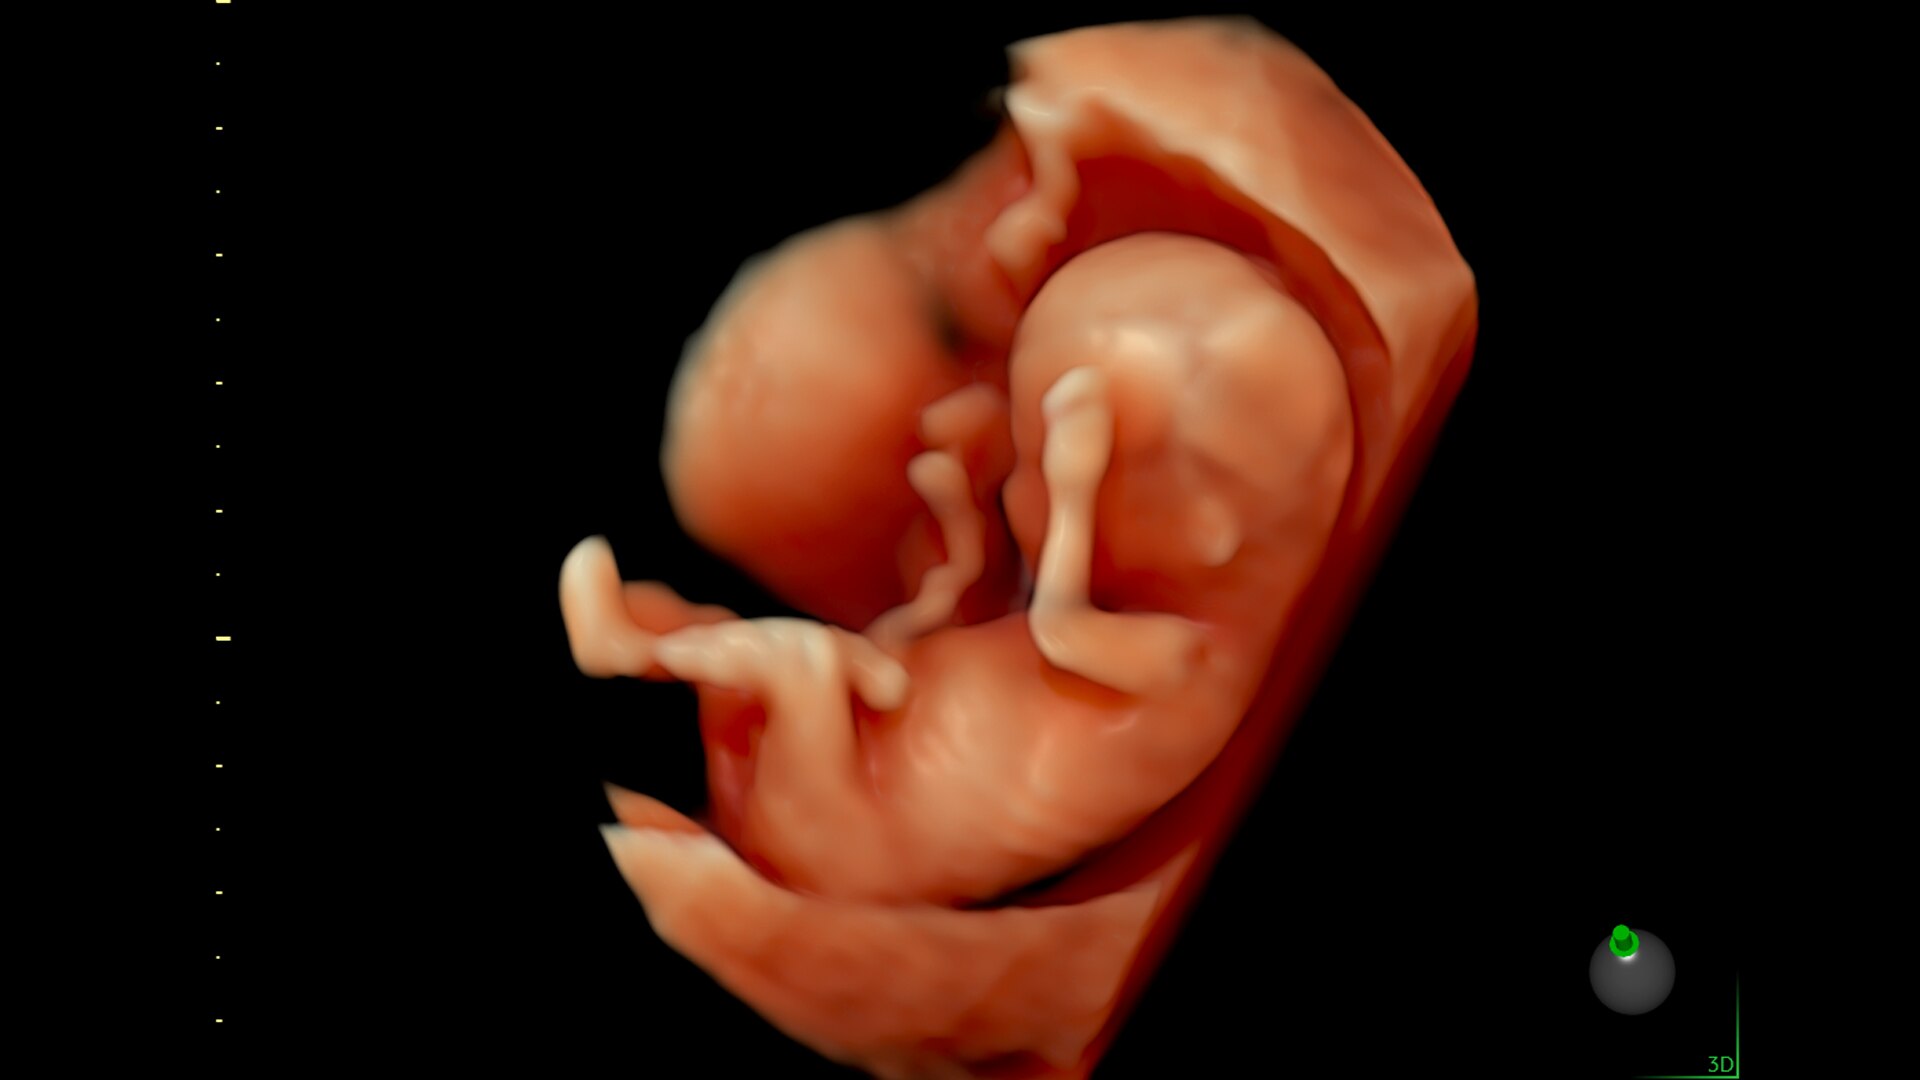

Fast, easy 3D-like blood flow visualization

Next level color Doppler that delivers exceptional sensitivity for easy, fast visualization of blood flow, displaying a 3D like appearance as seen in this 27-week fetal heart.